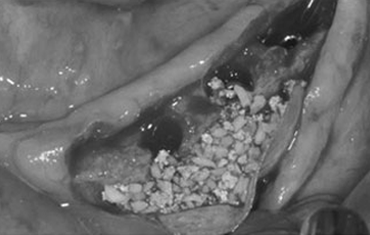

타 치과의 뼈 이식 후 골조직

램브란트치과 상인점 뼈이식 후 골조직